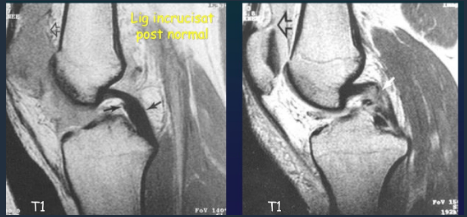

Rupture of cruciate ligaments